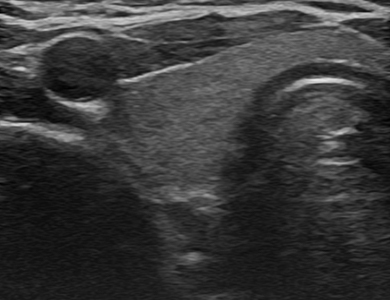

ÃÊÀ½ÆÄ »çÁø

¿ìÃø Á¤»ó °©»ó¼±

img

ÁÂÃø Á¤»ó °©»ó¼±

Á¤»ó °©»ó¼± ÇùºÎ